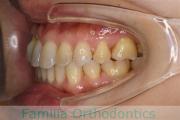

No.19V-044

- 主な症状:

- 上顎前突

- 年齢:

- 13歳

- 性別:

- 女性

- 抜歯部位

- 上:

- 44

- 下:

- 8558

- 主な使用装置:

- FEA

- 治療にかかった費用:

- 85万円

出っ歯を治したいということで小学生の時に来院されました。中学生になるまで経過観察をして、診断、上下左右から小臼歯を抜歯してマルチブラケット法にて治療を行いました。2年強、30回程度の通院が必要でした。

口元の突出感も大きく改善しています。

上下とも前歯の叢生(でこぼこ、凹凸、ガタガタ)がありましたので、保定をしっかりやらないと後戻りのリスクが出てきます。